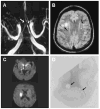

Conclusions: Rash or CSF pleocytosis is not required to diagnose varicella zoster virus (VZV) vasculopathy, whereas MRI/CT abnormalities are seen in almost all patients. Most patients had mixed large and small artery involvement. Detection of anti-VZV IgG antibody in CSF was a more sensitive indicator of VZV vasculopathy than detection of VZV DNA (p < 0.001). Determination of optimal antiviral treatment and benefit of concurrent steroid therapy awaits studies with larger case numbers.